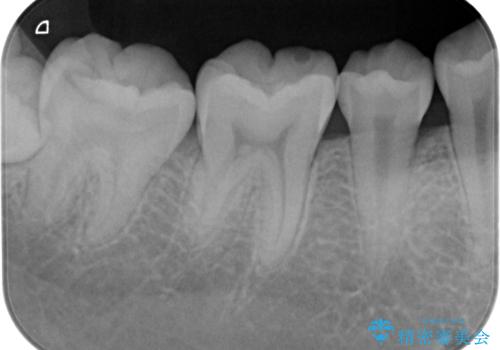

- 検査の結果虫歯が見つかった患者様です。

親知らずを抜歯してから虫歯を除去した後、ゴールドの詰め物で修復します。

比較的大きな虫歯でしたがゴールドでの修復にすることで歯の削る量を抑え、精度の高い治療を行うことができました。

親知らずの問題も同時に解決することで今後の虫歯リスクを抑えています。